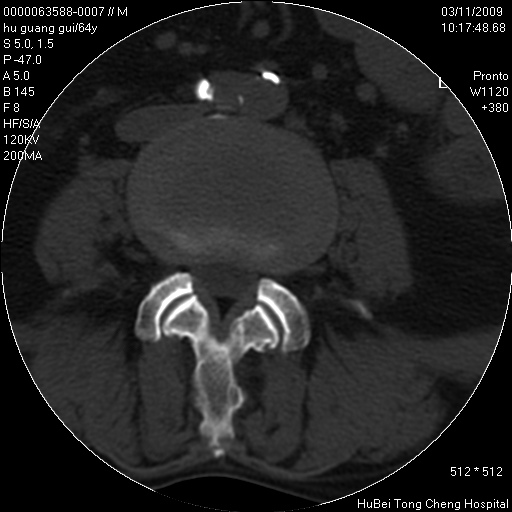

患者 男,64岁。腰痛十余天。(临床未提供其他病史)

临床诊断:腰痛原因待查(腰椎间盘突出症?)。

腰椎间盘ct轴位平扫(层厚5mm,层距4mm),图像如下:

腰椎退行性变,腰4—5椎间盘膨出。

右侧骶骨侧块骨侵蚀,骶髂关节骨性关节面破坏,并见软组织肿块,考虑骨转移瘤可能,进一步检查。

1.腰椎退行性变,腰4—5椎间盘膨出。

2.右侧骶骨侧块骨侵蚀,骶髂关节骨性关节面破坏,并见软组织肿块,考虑:脊索瘤,骨转移瘤可能,进一步检查。

1)腰椎退行性变,l4—5椎间盘膨出。2)骶骨右侧块骨转移瘤可能,3)水平骶椎。建议作一步检查。